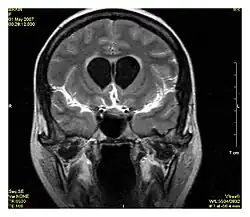

Neuroimagem

A ressonância magnética é a ferramenta investigativa de escolha para cânceres neurológicos, pois tem melhor resolução do que a TC e oferece uma melhor visualização da fossa posterior. O contraste fornecido entre matéria cinza e branca torna a ressonância magnética melhor opção para muitas condições do sistema nervoso central, incluindo doenças desmielinizantes, demência, doença cerebrovascular, doenças infecciosas e epilepsia.[30] Uma vez que muitas imagens são retiradas em milisegundos, mostra como o cérebro responde a diferentes estímulos, permitindo que os pesquisadores estudem as anormalidades cerebrais funcionais e estruturais em distúrbios psicológicos.[31] A RM também é utilizada na cirurgia estereotáxica guiada por MRI e radiocirurgia para o tratamento de tumores intracranianos, malformações arteriovenosas e outras condições tratáveis cirurgicamente usando um dispositivo conhecido como N-localizer.[32][33][34][35][36][37][38][39][40][41][42][43][44][45]